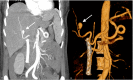

Figure 3

Figure 3. CTA (A) and 3D angiographic study (B) reconstruction of the abdomen showing the presence of a pseudoaneurysm is documented in a segmental branch of the right hepatic artery with a diameter greater than approximately 12 mm (arrows); a biliary stent previously placed in the common bile duct can also be seen

CTA: computed tomography angiography; 3D: three-dimensional